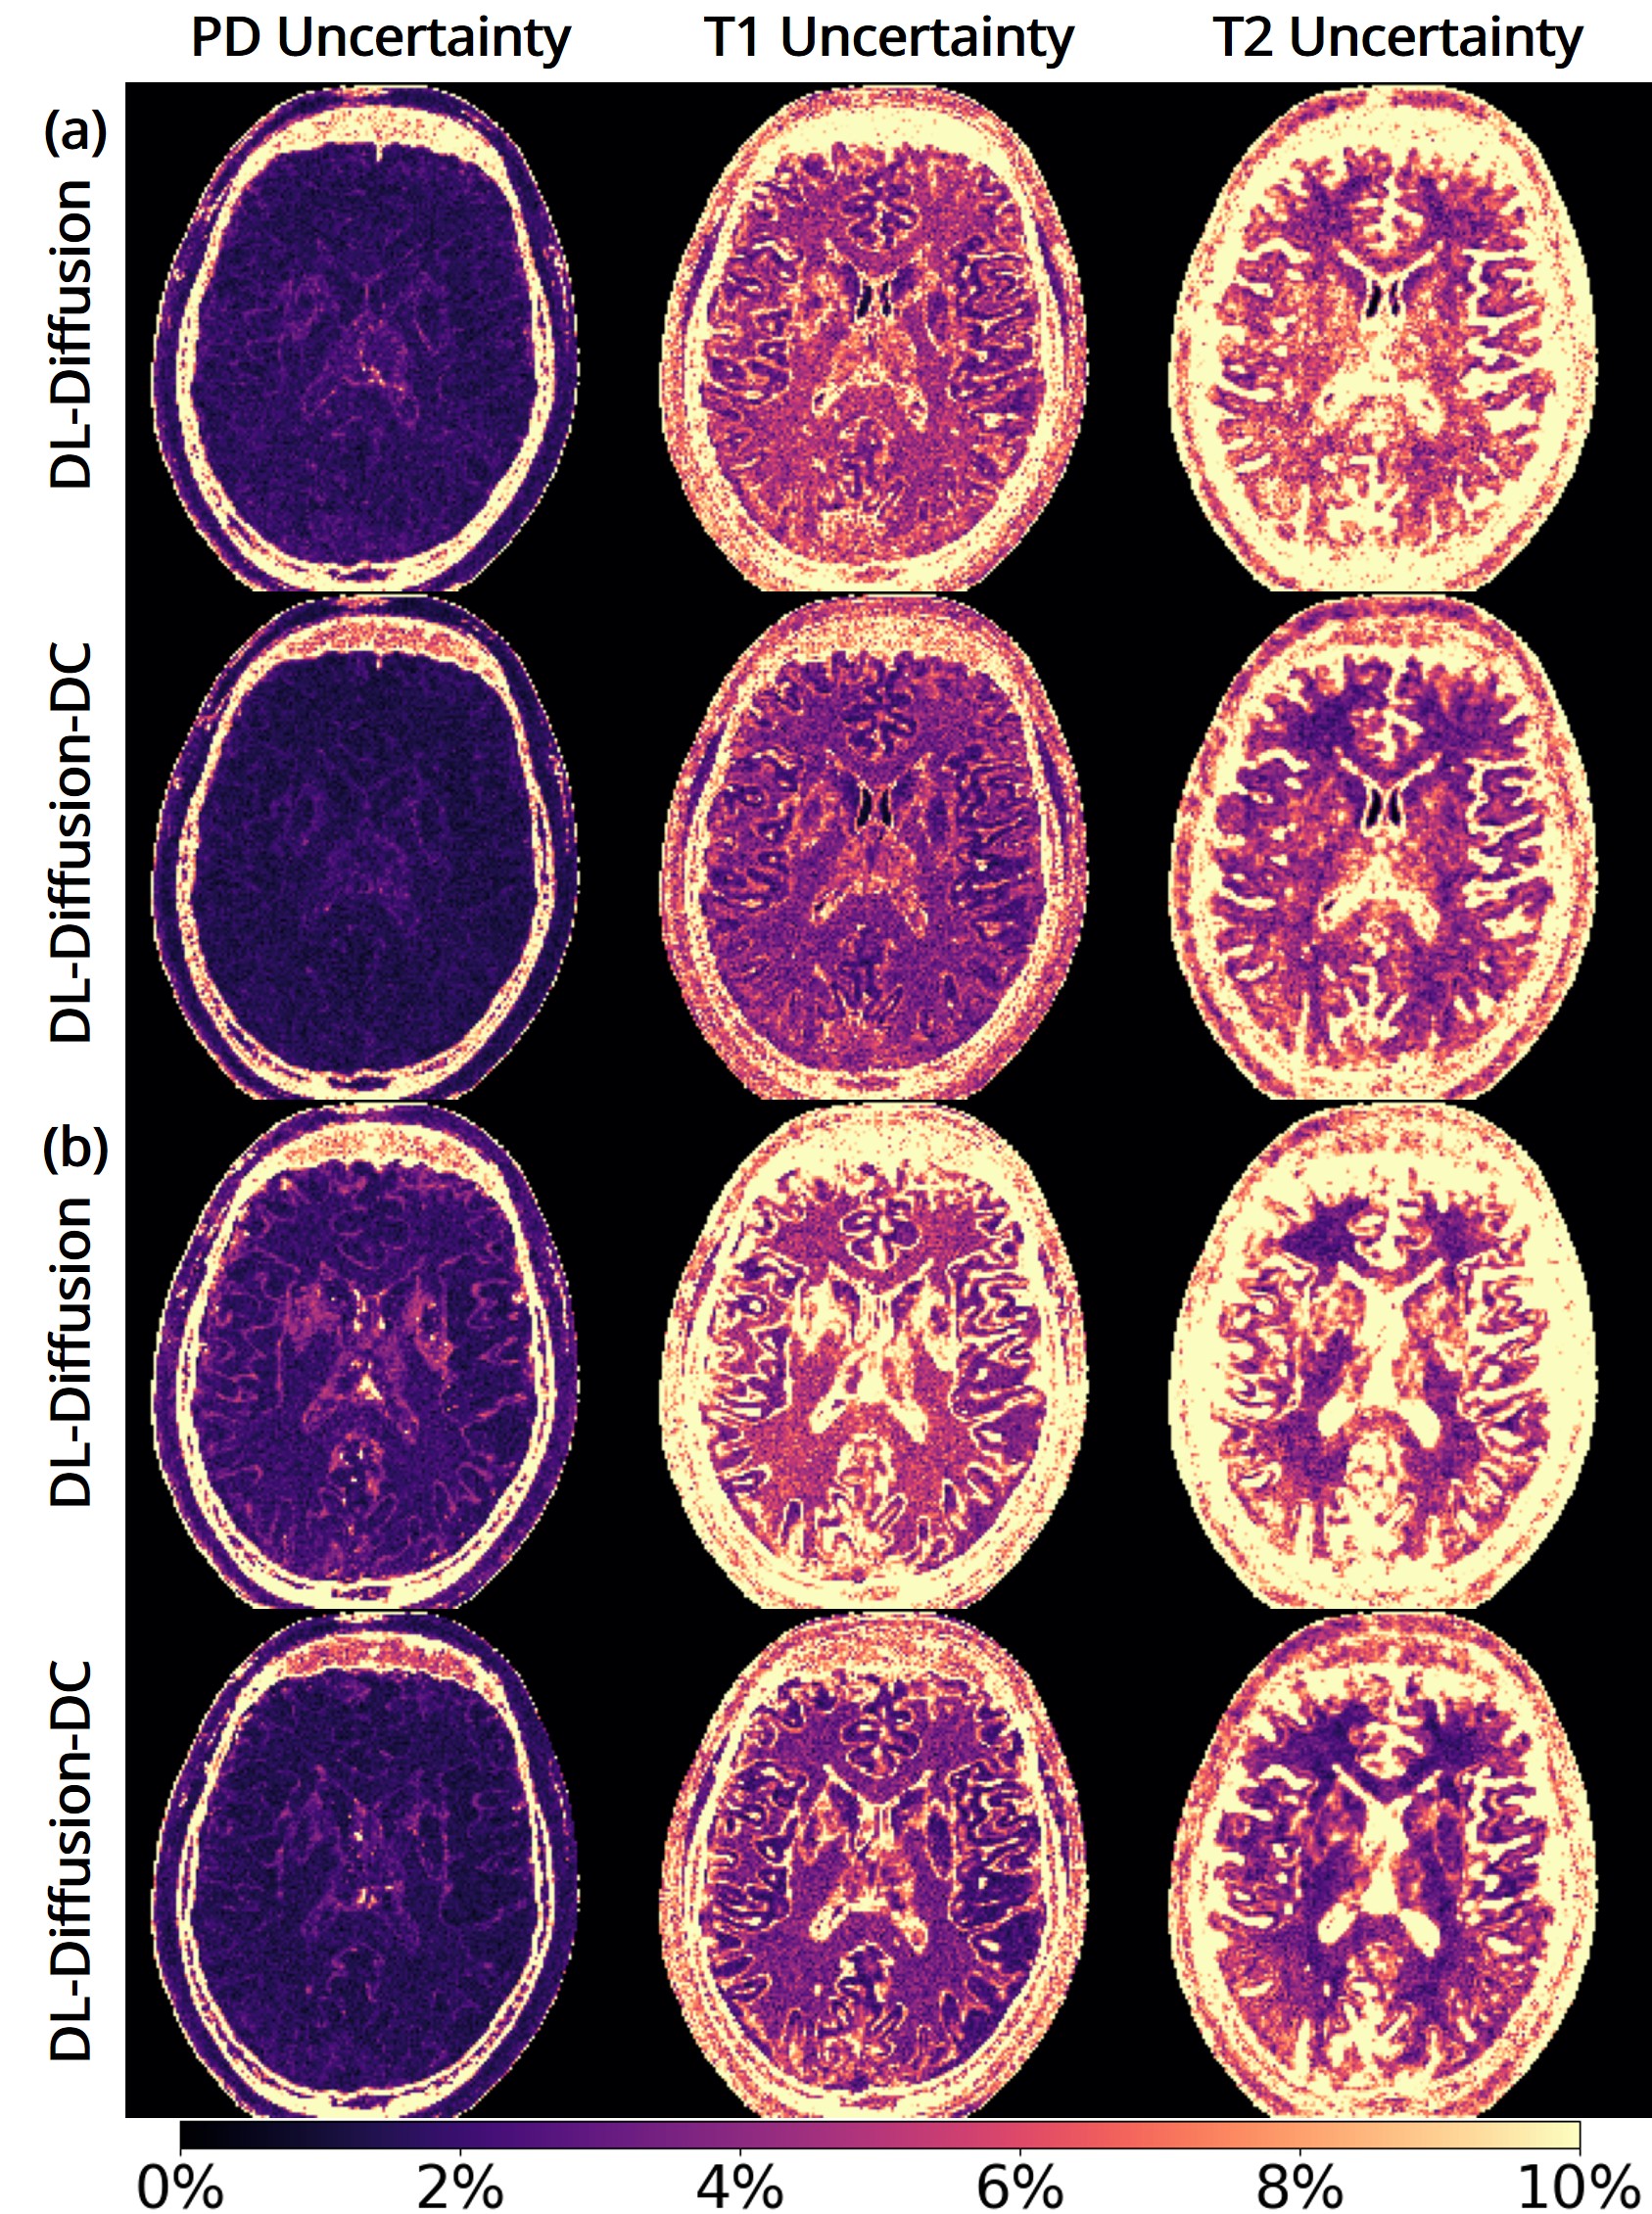

The 3D fast silent multi-parametric mapping sequence with zero echo time (MuPa-ZTE) is a novel quantitative MRI (qMRI) acquisition that enables nearly silent scanning by using a 3D phyllotaxis sampling scheme. MuPa-ZTE improves patient comfort and motion robustness, and generates quantitative maps of T1, T2, and proton density using the acquired weighted image series. In this work, we propose a diffusion model-based qMRI mapping method that leverages both a deep generative model and physics-based data consistency to further improve the mapping performance. Furthermore, our method enables additional acquisition acceleration, allowing high-quality qMRI mapping from a fourfold-accelerated MuPa-ZTE scan (approximately 1 minute). Specifically, we trained a denoising diffusion probabilistic model (DDPM) to map MuPa-ZTE image series to qMRI maps, and we incorporated the MuPa-ZTE forward signal model as an explicit data consistency (DC) constraint during inference. We compared our mapping method against a baseline dictionary matching approach and a purely data-driven diffusion model. The diffusion models were trained entirely on synthetic data generated from digital brain phantoms, eliminating the need for large real-scan datasets. We evaluated on synthetic data, a NISM/ISMRM phantom, healthy volunteers, and a patient with brain metastases. The results demonstrated that our method produces 3D qMRI maps with high accuracy, reduced noise and better preservation of structural details. Notably, it generalised well to real scans despite training on synthetic data alone. The combination of the MuPa-ZTE acquisition and our physics-informed diffusion model is termed q3-MuPa, a quick, quiet, and quantitative multi-parametric mapping framework, and our findings highlight its strong clinical potential.💡 Summary & Analysis